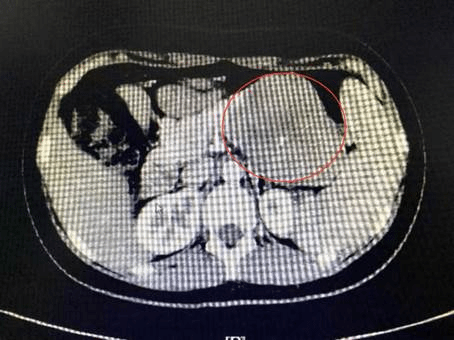

红圈处为肿瘤

孙铁为教授介绍,“隐居”在腹膜后的胰腺是一个后腹膜器官,解剖位置深,周围器官复杂、大血管多。此病例的胰体尾部直径约11公分的肿瘤紧紧被脾血管包绕,与脾血管起始部位关系密切,保留脾脏困难。由于肿瘤巨大,且临近腹腔干及脾动脉起始部,操作空间狭窄,术中以腹腔镜建立胰后隧道离断胰腺颇有难度。传统手术需要在腹部切一个20-30厘米的切口,对身体伤害较大。但在腹腔镜下切除如此巨大的肿瘤,稍有不慎即可导致脾血管的撕裂,造成术中大出血,危及患者生命。最终结合患者意愿,经讨论决定实施3D腹腔镜下的胰体尾切除和脾切除术。